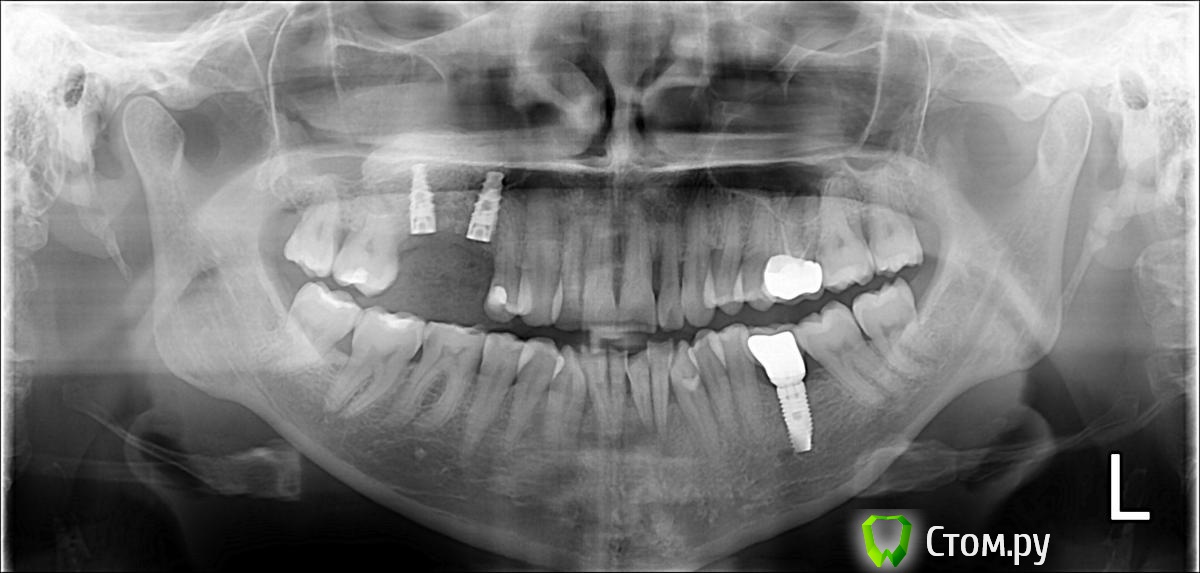

prioks Опубликовано 26 апреля, 2014 Поделиться Опубликовано 26 апреля, 2014 Здравствуйте! Нужен совет. Вчера проведен открытый синус-лифтинг с установкой имплантов. Важно мнение специалистов по результатам снимка. Не близко ли расположен имплант к зубу и общая характеристика данной ситуации.Спасибо! Ссылка на комментарий

red_butler Опубликовано 26 апреля, 2014 Поделиться Опубликовано 26 апреля, 2014 панорамный снимок дает искажения, для ответа на ваш вопрос нужны прицельные снимки под разными углами Ссылка на комментарий